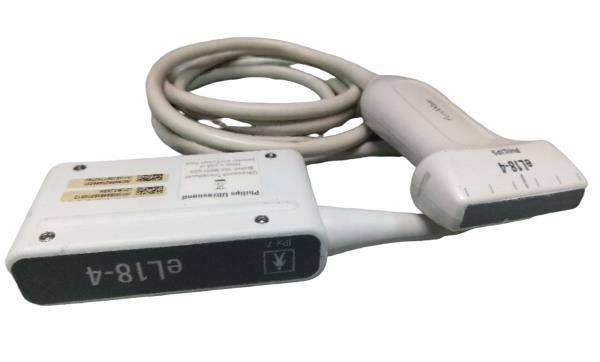

Optional: linear/transvaginal/micro-cardiac/rectal/printer